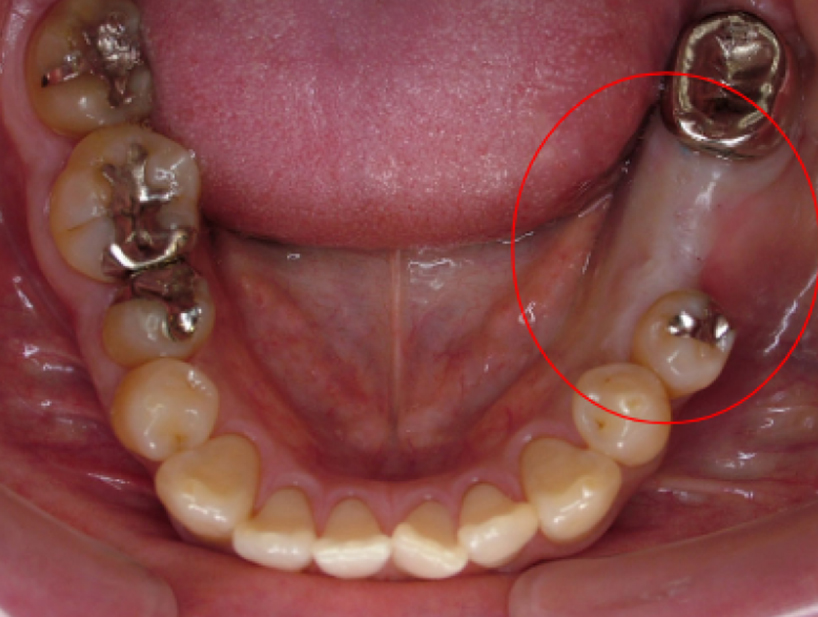

治療前治療後

| 治療内容 | インプラント奥歯1本・根管治療・矯正治療(圧下) |

|---|---|

| 患者様の年齢 | 40歳 |

| 患者様の性別 | 男性 |

| 治療期間 | 1年 |

| 治療回数 | 矯正治療合わせて50回程度 |

| 治療費用 | 根管治療1歯6万円/インプラント治療1歯50万円 矯正治療:1歯 10万円 |

| 治療で得られるメリット |

|

| 治療する際に起こる リスク・副作用 |